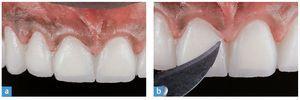

Se retira el dique de goma y se corrige la oclusión mediante un sistema de pulidores de diamante para cerámica. El tejido gingival sano estaba estable al cabo de dos semanas (figs. 35 y 36). Las figuras 37 y 38 muestran la sonrisa del paciente seis meses después del cementado.

Fig. 35. La imagen de detalle muestra el perfil de emergencia y el estado periodontal sano del incisivo central izquierdo.

Fig. 36. La situación al cabo de tres meses.